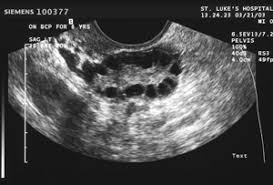

基礎濾泡(AF, antral follicle):

月經前5天以陰道超音波檢測‧

AF大小: 2-5mm